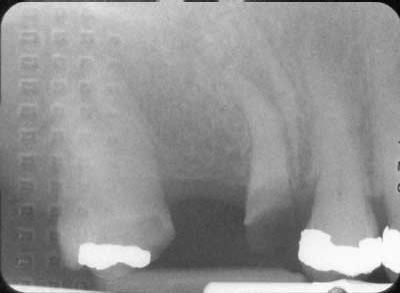

If the patient is at high risk —

Possible inadequate saliva flow, evident cavitation and radiographic lesions, and a high number on the bacterial test will require a multiple approach and a staged treatment plan.